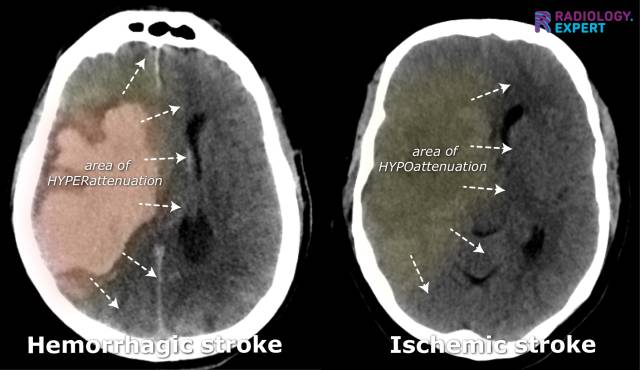

In cases of clinical suspicion of a stroke, a non-contrast CT scan of the brain is generally performed first: a 'non-contrast CT' (Fig. 12). The main objective is to distinguish between an ischemic and a hemorrhagic stroke and to rule out other abnormalities (such as space-occupying lesions). A non-contrast CT brain has a high sensitivity for detecting intracerebral hemorrhages. However, the brain parenchyma often shows few abnormalities in the first hours of a cerebral infarction. Nonetheless, there should always be a search for (subtle) CT abnormalities that may indicate ischemia. Any occlusion's presence, extent, and location are difficult to determine on a non-contrast CT scan.

Figure 12. Non-contrast CT brain. Hemorrhagic stroke vs. ischemic stroke.